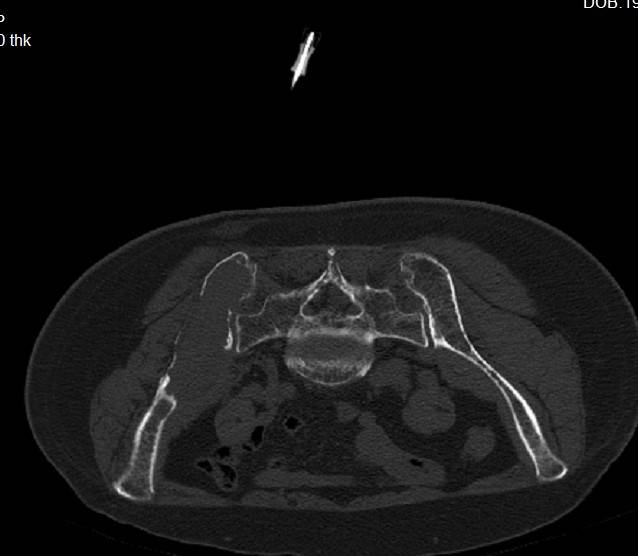

骨盆MRI:骨盆诸骨多发异常强化信号影伴右侧髂骨软组织信号,考虑恶性肿瘤。

PET-CT:右侧髂骨明显骨质破坏伴软组织形成,放射性摄取异常增高(SUVmax=21.20),全身多骨(颅骨、脊柱、肋骨、锁骨、肩胛骨、四肢骨近端等)可见多发放射性摄取增高灶(SUVmax=11.62),提示多发性溶骨性病变。